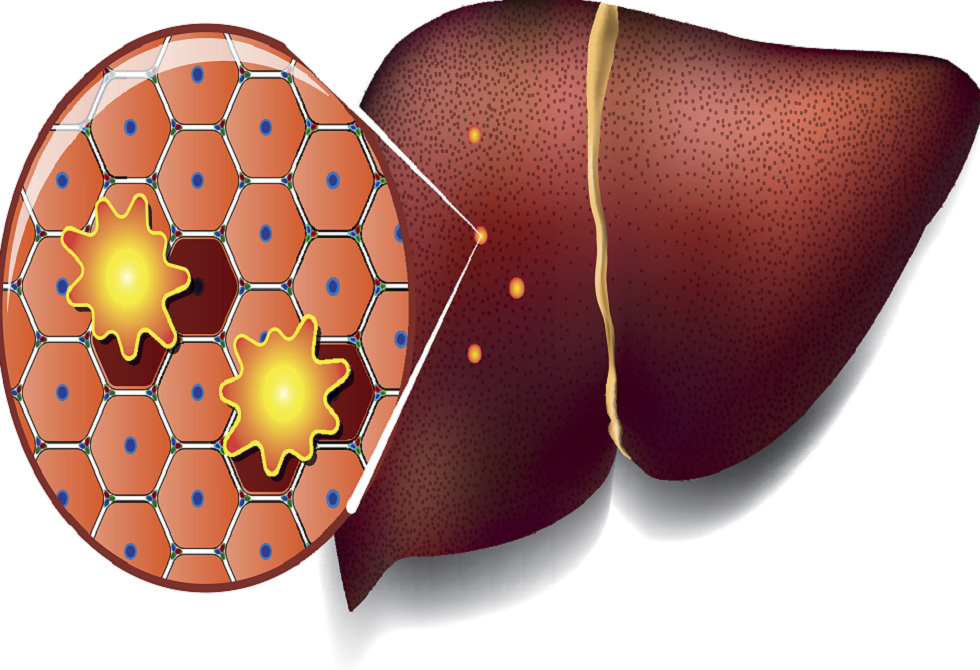

النظام الغذائي الغني بالدهون قد يهيئ الكبد للإصابة بالسرطان

كشف فريق من العلماء أن الدهون غير الصحية الشائعة في الأطعمة المصنعة تعرّض خلايا الكبد لإجهاد مزمن.

وهذا الإجهاد يجبر الكبد على الدخول في حالة "البقاء"، حيث يتوقف عن أداء وظائفه الطبيعية مثل تنقية الدم ومعالجة العناصر الغذائية وإزالة السموم، ويكتفي بمواجهة الضغط الناتج عن النظام الغذائي السيئ. ومع مرور الوقت، تتراجع خلايا الكبد إلى حالة بدائية تشبه الخلايا الجنينية، مستعدة للنمو السريع، لكنها تفقد القدرة على أداء وظائفها الحيوية بشكل كامل.

وأظهرت دراسة أجراها علماء من معهد ماساتشوستس للتكنولوجيا وجامعة هارفارد على الفئران، أن هذا الإجهاد الغذائي يؤدي إلى إعادة برمجة بطيئة لخلايا الكبد على مدى 15 شهرا. وبعد ستة أشهر فقط، بدأت خلايا الكبد المجهدة في الاستعداد للإصابة بالسرطان، حيث فُتحت مناطق من الحمض النووي تتحكم في نمو الخلايا، ما يضع التعليمات الجينية للسرطان في حالة تأهب قصوى، قبل سنوات من ظهور الورم.

وللتأكد من صحة النتائج لدى البشر، حلل العلماء عينات كبد من مرضى الكبد الدهني (MASLD) في مراحل مختلفة، بعضهم أصيب لاحقا بسرطان الخلايا الكبدية.

وأظهرت التحليلات علامات إعادة البرمجة الخلوية نفسها التي لوحظت في الفئران، وارتبطت قوة المؤشرات الجزيئية بارتفاع احتمالية الإصابة بالسرطان خلال 10–15 عاما.

ويعد سرطان الخلايا الكبدية أكثر أنواع سرطان الكبد شيوعا، ويصعب اكتشافه في مراحله المبكرة بسبب قلة الأعراض. وقد تشمل العلامات المبكرة فقدان الوزن غير المبرر وفقدان الشهية أو الشعور بالامتلاء بعد وجبة صغيرة. ومع تقدم المرض، قد تظهر أعراض مثل اليرقان والتعب والغثيان وسهولة النزف أو الكدمات وانتفاخ البطن نتيجة تراكم السوائل.

وتشير الدراسة إلى أن الإجهاد الغذائي الطويل الأمد قد يهيئ الكبد لتطور السرطان قبل ظهور أي أورام، مؤكدة أهمية الحد من استهلاك الدهون المشبعة والأطعمة المصنعة، ومتابعة صحة الكبد بانتظام، خاصة لدى الأفراد الذين لديهم عوامل خطر مثل مرض الكبد الدهني المزمن أو التهاب الكبد أو تليف الكبد.

نشرت الدراسة في مجلة Cell.

المصدر: ديلي ميل